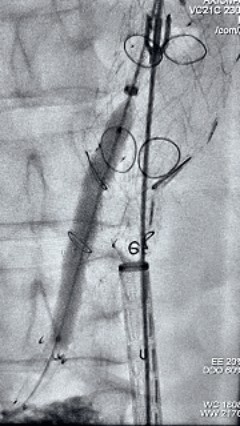

采用G-Branch胸腹主动脉覆膜支架隔绝瘤体,重建内脏区分支。主体使用TAAA3418120e7i1010,腹腔干和肠系膜上动脉分别植入直径10mm覆膜支架,右肾直径6mm支架,左肾直径7mm支架

G-Branch在本例手术中展现出对扭曲解剖结构的出色适应性,针对该患者严重扭曲的瘤颈,支架系统的优异柔顺性使其能够顺利通过复杂路径,完成内脏分支血管的重建。

其独特的双内嵌、双外翻混合多分支设计兼顾了操作效率与结构可靠性,预置导丝系统简化了肠系膜上动脉(SMA)和腹腔干动脉(CA)的超选流程,显著提高手术效率。